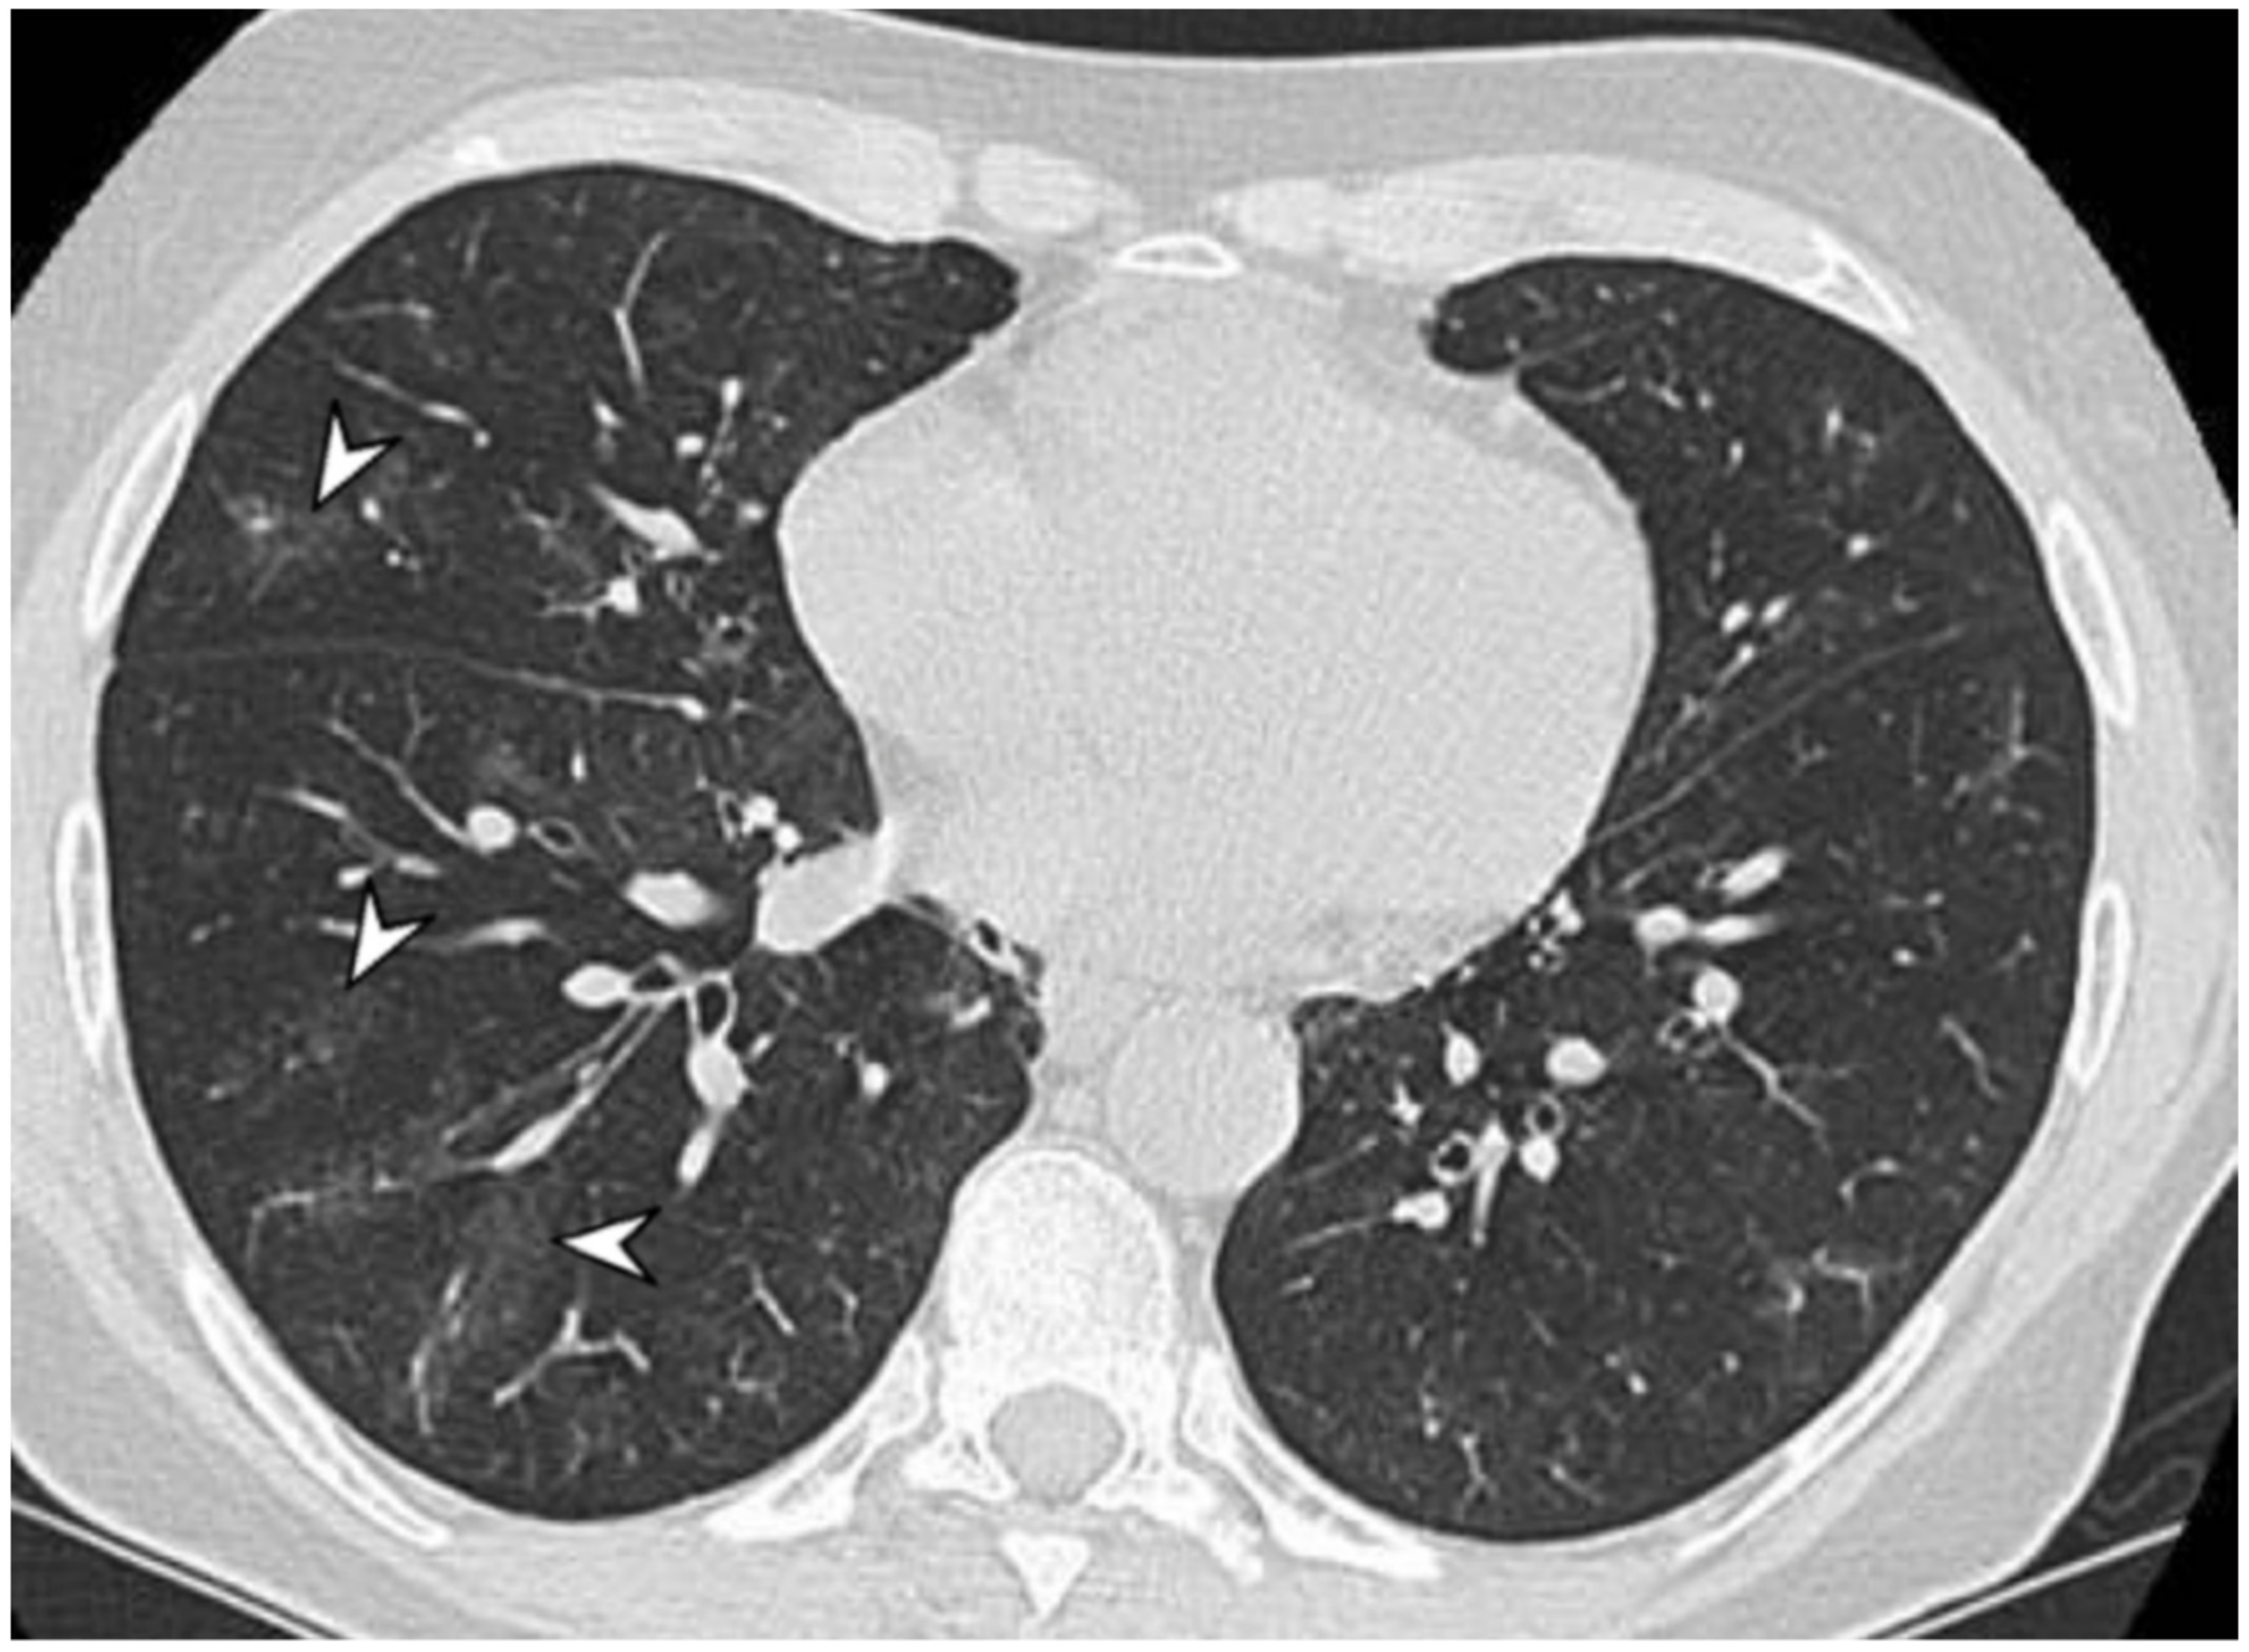

2.4. Granulomatosis with Polyangiitis (GPA-Wegener’s Disease)

| GPA | Solid nodules, GGOs due to hemorrhagic alveolitis (common); halo sign, crazy paving (less common) |